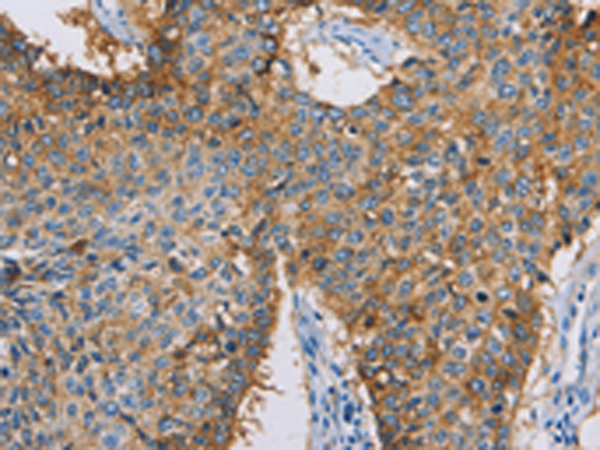

分类: 科研抗体货号: P04734别名: GVI; PLA2; INAD1; NBIA2; iPLA2; NBIA2A; NBIA2B; PARK14; PNPLA9; CaI-PLA2; IPLA2-VIA; iPLA2beta应用: IHC反应种属: Human, Mouse, Rat